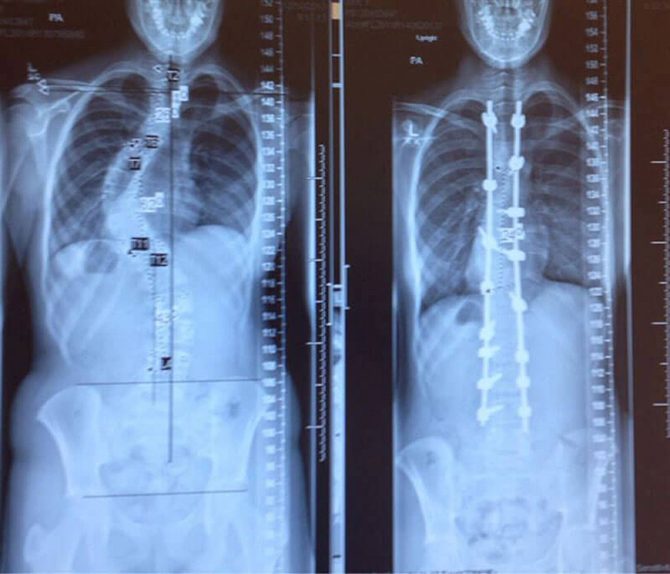

Позвоночник одного и того же человека до и после лечения сколиоза.